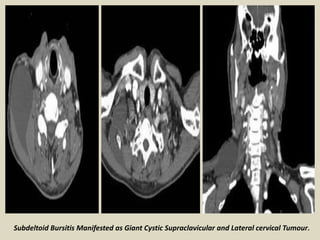

Subdeltoid Bursitis Manifested as Giant Cystic Supraclavicular and Lateral cervical Tumour.